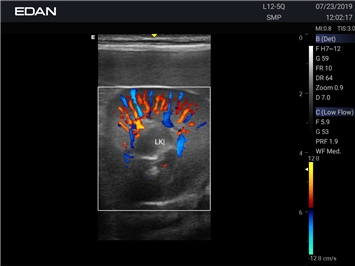

EDAN Acclarix AX2 VET представляет собой специализированную ветеринарную ультразвуковую систему, сочетающую высокую производительность с доступной ценой. Благодаря продуманной конструкции и передовым технологиям, система обеспечивает качественную диагностику животных различных видов.

Революционная платформа визуализации:

• Высокое разрешение для детальной диагностики

• Улучшенная визуализация глубоко расположенных органов

• Технология адаптивной визуализации тканей:

• Непрерывная автоматическая оптимизация изображения

• Адаптация к особенностям анатомии разных видов животных

• Повышенная точность исследований

Цветовой допплер:

Да

Энергетический допплер: